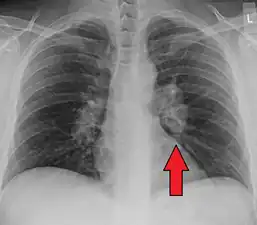

Hilar adenopathy especially on the person's left (AP CXR)

Hilar adenopathy especially on the person's left (lateral CXR)

Chest radiograph changes are divided into four stages:[104]

- bihilar lymphadenopathy

- bihilar lymphadenopathy and reticulonodular infiltrates

- bilateral pulmonary infiltrates

- fibrocystic sarcoidosis typically with upward hilar retraction, cystic and bullous changes

Although people with stage 1 radiographs tend to have the acute or subacute, reversible form of the disease, those with stages 2 and 3 often have the chronic, progressive disease; these patterns do not represent consecutive "stages" of sarcoidosis. Thus, except for epidemiologic purposes, this categorization is mostly of historic interest.[28]